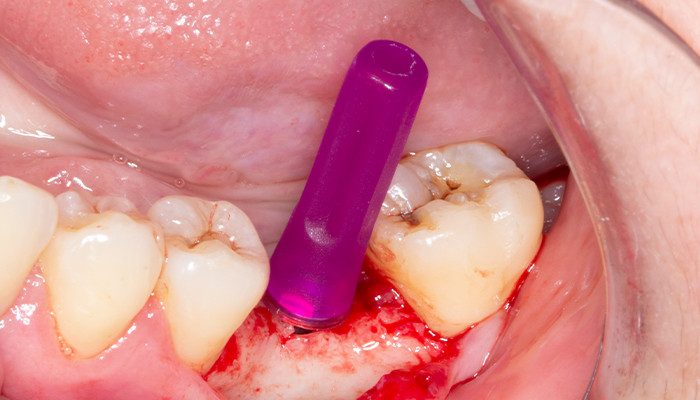

6 | Checagem dimensional da perfuração realizada utilizando os paralelizadores.